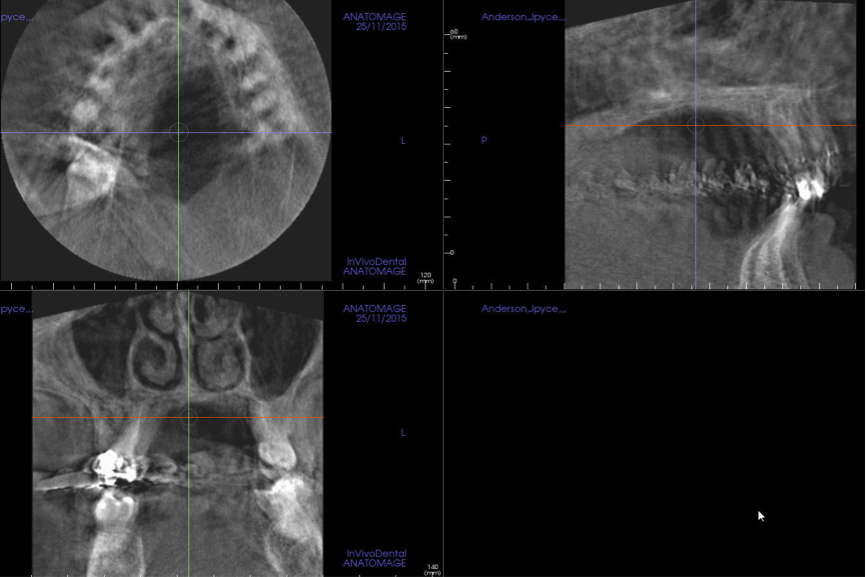

(5.) Sagittal orthogonal section of the maxillary midline showing a developing mass in the posterior pharyngeal wall. This is posterior pharyngeal tonsilar hypertrophy (hypertrophic ad- enoids), which is causing significant narrowing of the airway at the level of the naso-pharynx.

Figure 5